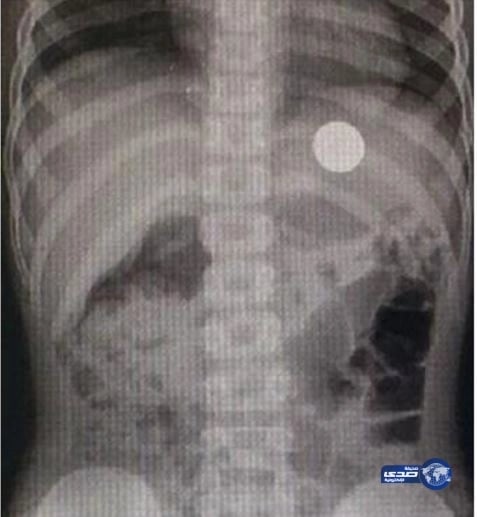

بالصور.. فريق طبي ينجح في استخراج عملة معدنية من صدر طفل ببريدة